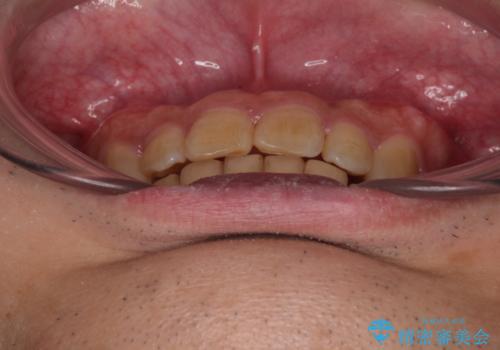

骨格性のディープバイト 補助装置を併用したワイヤー矯正治療で咬み合わせを改善

- 前歯のデコボコと深い咬み合わせを気にして来院された患者様です。

骨格的に上顎骨がやや前方にあり、それが原因で下顎前歯が隠れるほどのディープバイトになっている状態でした。